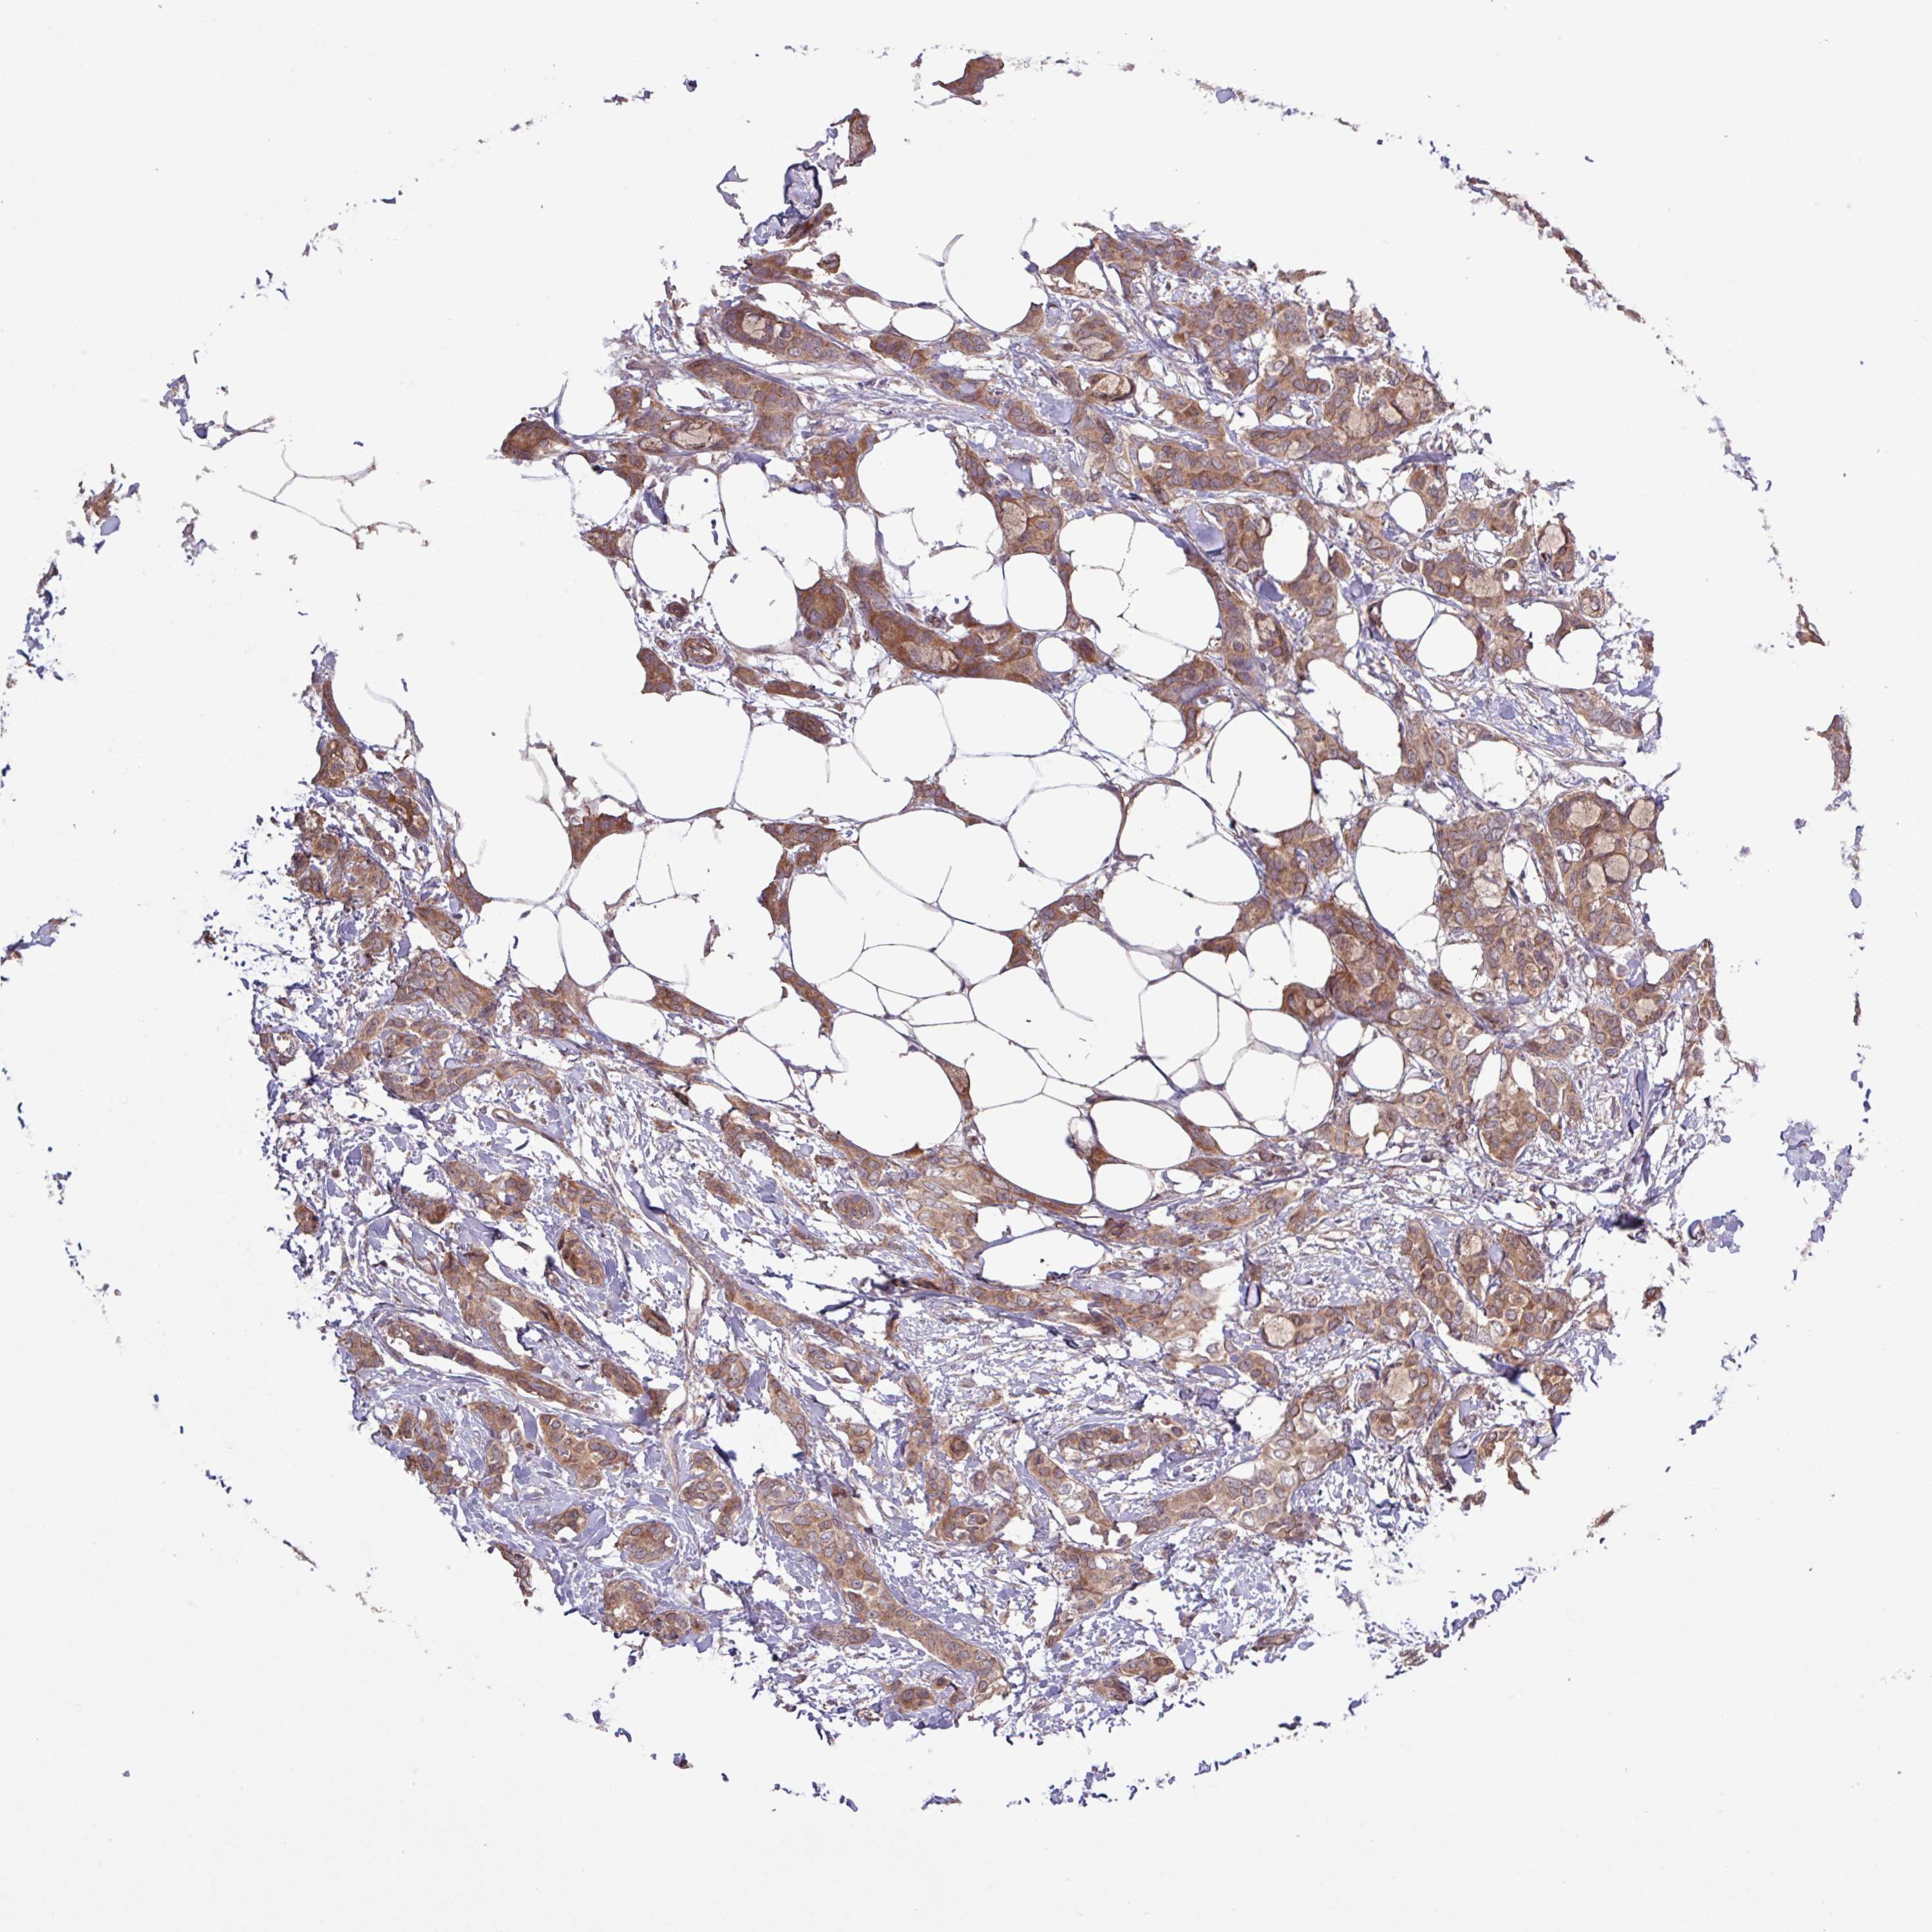

BRCA TCGA BRCA VALIDATION PROTEIN EXPRESSION

ANTIBODIES

AND

VALIDATION